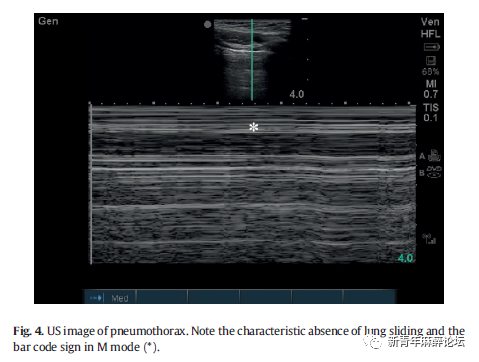

2.4. 附加步骤:张力性气胸和 FAST

张力性气胸是一个引起非创伤性心脏骤停较为罕见的原因,临床上诊断较为容易[18]。在CPR中,急诊医生应在(超声下)双侧胸前区检查是否肺滑动征消失(Fig.4)。如果诊断出气胸,应考虑进行胸腔穿刺减压或胸腔闭式引流术。在CPR过程中,可能因肋骨骨折引起临床上不明显的少量气胸,临床医生应意识到这些损伤可能并不需要急救介入治疗。